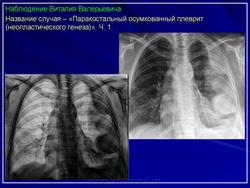

2. Осумкованный паракостальный плеврит.

Пристеночные (паракостальные) осумкованные плевриты являются результатом неполного рассасывания свободного экссудативного паракостального плеврита или транссудата, свои широким основанием прилежат к поверхности ребер.

В типичных случаях рентгенологическая картина пристеночных осумкований довольно характерна.

Они, скиалогически проявляясь синдромом «ограниченного затемнения», имеют форму теней, примыкающих широким плоским основанием к реберному краю.